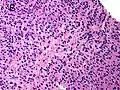

Gleason Pattern 3. H&E stain.

• Pattern 3 - The tissue still has recognizable glands, but the cells are darker. At high magnification, some of these cells have left the glands and are beginning to invade the surrounding tissue or having an infiltrative pattern. This corresponds to a moderately differentiated carcinoma.

Gleason 3

Gleason 3 is a clearly infiltrative neoplasm, with extension into adjacent healthy prostate tissue. The glands alternate in size and shape, and are often long/angular. They are usually small/micro-glandular in comparison to Gleason 1 or 2 grades. However, some may be medium to large in size. The small glands of Gleason 3, in comparison to the small and poorly defined glands of pattern 4, are distinct glandular units. Mentally you could draw a circle around each of the glandular units in Gleason 3.[4][7]